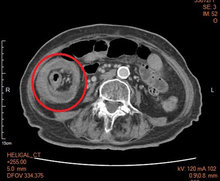

82 歲陳姓阿嬤,腹脹、腹痛反覆發作長達近3個月,期間體重也減輕5至6公斤,同時伴隨貧血,她到醫院進行住院檢查及輸血治療,結果從腹部電腦斷層看到大常出現腸套疊病兆,醫師緊急進行手術切除,術中發現病人患大腸癌,所幸病理呈現為初期癌症,因此阿嬤術後恢復良好,已順利出院,後續只需要定期追蹤腸癌症狀即可。

烏日新林醫院大腸直腸外科主任劉添裕表示,患者在做大腸鏡檢查時,在大腸肝曲處出現腸腫瘤,並伴隨部分阻塞,切片檢驗後病理為惡性;另外在進行腹部電腦斷層後,右側大腸腫瘤伴腸套疊在肝曲處,可見呈同心圓腸套疊病兆!因此緊急會診後,接受右半大腸切除吻合手術處理。

劉添裕主任透露,手術中發現患者3公分大腸癌就在右下迴盲瓣上方,套疊到右上方肝曲處,情況相當危急,所幸順利接受右半大腸切除及淋巴腺清除,病理呈現為第1期大腸癌,只需定期追蹤,實屬不幸中的大幸。